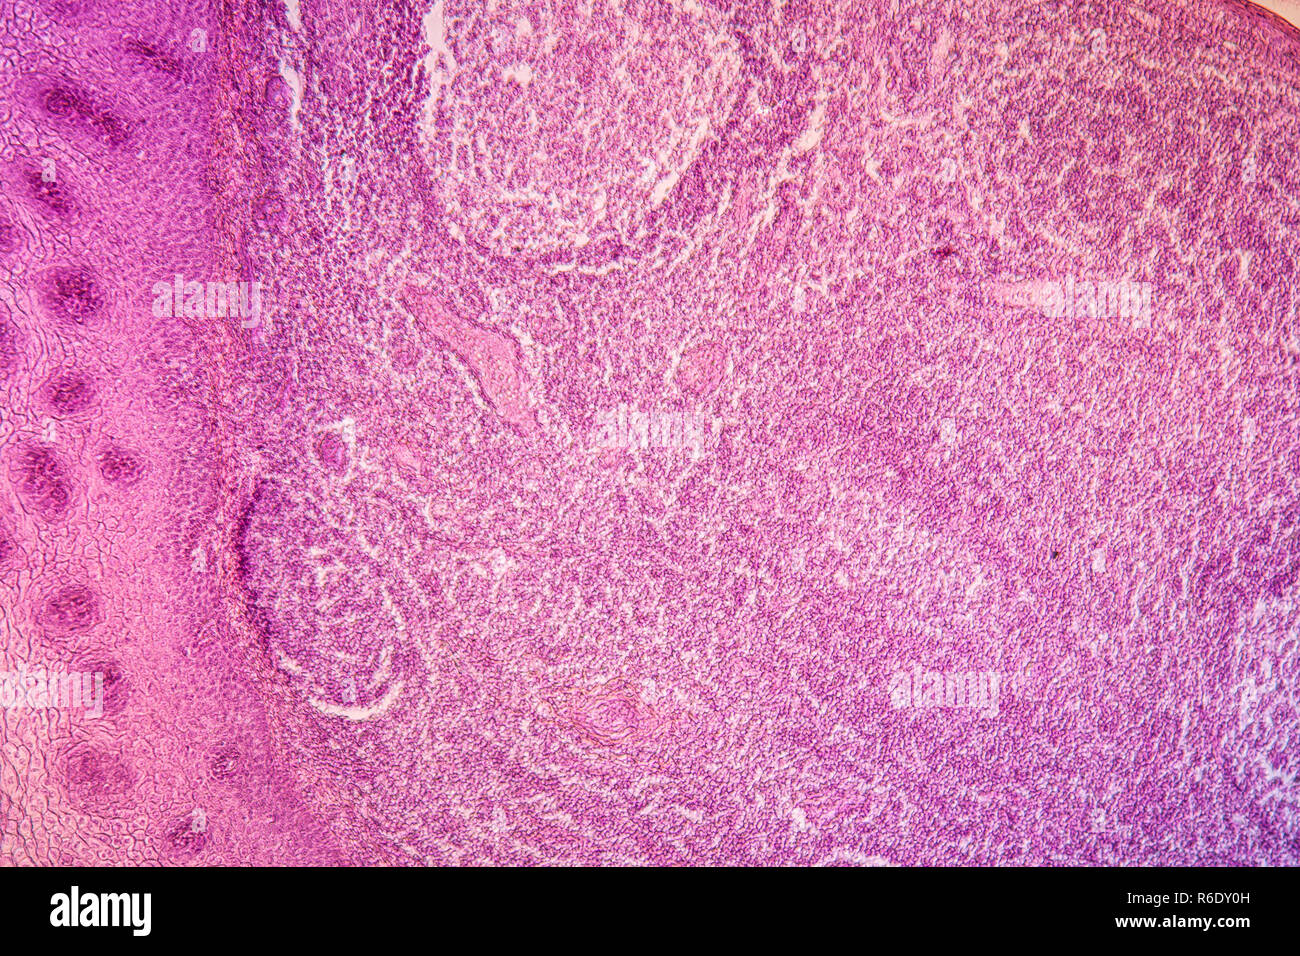

Mandelentzündung krankes Gewebe unter dem Mikroskop 100x Stockfotohttps://www.alamy.de/image-license-details/?v=1https://www.alamy.de/mandelentzundung-krankes-gewebe-unter-dem-mikroskop-100x-image274312906.html

Mandelentzündung krankes Gewebe unter dem Mikroskop 100x Stockfotohttps://www.alamy.de/image-license-details/?v=1https://www.alamy.de/mandelentzundung-krankes-gewebe-unter-dem-mikroskop-100x-image274312906.htmlRMWX80WE–Mandelentzündung krankes Gewebe unter dem Mikroskop 100x